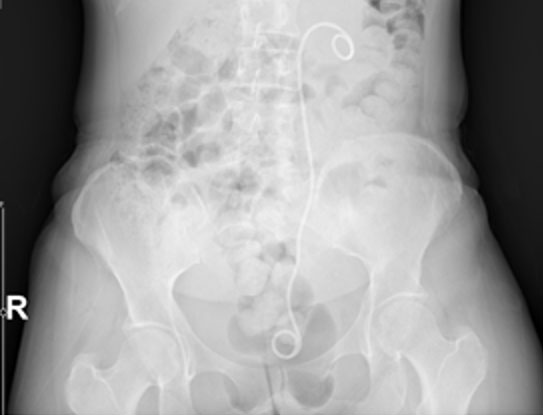

Ameliyat Öncesi: Röntgende sol üreterde katater dışında anlamlı görüntü yok iken, MR’da sol sakroiliak eklem seviyesinde düzensiz sınırlı, içinde gaz gölgesi olan ve mesaneyi iten büyük yumuşak doku kitlesi görülmekte.

Röntgende sol üreterde katater dışında anlamlı görüntü yok iken, MR’da sol sakroiliak eklem seviyesinde düzensiz sınırlı, içinde gaz gölgesi olan ve mesaneyi iten büyük yumuşak doku kitlesi görülmekte.